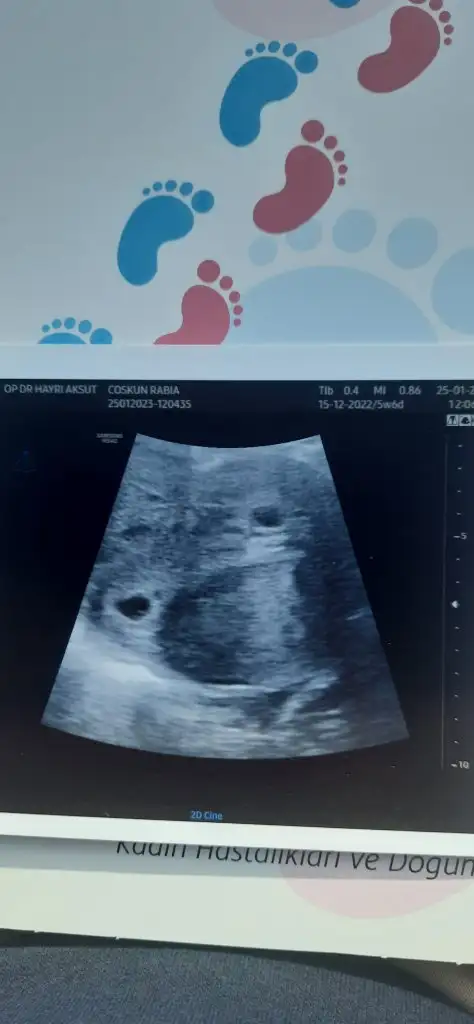

canım aynı durumu bende yaşadım ikiz olabilir dedi hatta sonra dur dedi alttan muayene edeyim dedi sonra yansıması dedi yanlış gördük dedi sonra ilerleyen haftalarda belli olur şimdilik bir tane dedi hayırlısı dedim. anlayacağın banada net konuşmadı. senin beta artışın nasıldı? sağolsun doktor arkadaşım 12. hafta görüşelim dedi yanından ayrıldıktan sonra eşim serzenişte bulundu 12. haftaya kadar hiç bişey yapılmayacak mı yok parasıyla deilmi neden bize 12. hafta gel dedi bende baktım herifim çok tır tır ediyor arada başka doktora gideriz dedim adamın yüzü güldü.İyi akşamlar hanımlar 7+4 haftalık gebeyim dün bebeğin kalp atışını gördük ama doktor iki bebek olabileceğini söyledi ama ikinci bebek olarak gördüğü şeyin bebeğin eşi olabileceginide söyledi böyle bir durum yaşayan var mı aranızda

Benimde alttan muayene ile gördü banada gösterdi ekrandan 2.bebek yada bebeği n eşi olabilir emin degilim dedi.Benim gebeliğim geç döllenme adet gecikmesinin 10. günü ilk değer 38 çıktı 3 gün sonra 370 pazartesi kendi doktoruma gidince netleşir durum herhaldecanım aynı durumu bende yaşadım ikiz olabilir dedi hatta sonra dur dedi alttan muayene edeyim dedi sonra yansıması dedi yanlış gördük dedi sonra ilerleyen haftalarda belli olur şimdilik bir tane dedi hayırlısı dedim. anlayacağın banada net konuşmadı. senin beta artışın nasıldı? sağolsun doktor arkadaşım 12. hafta görüşelim dedi yanından ayrıldıktan sonra eşim serzenişte bulundu 12. haftaya kadar hiç bişey yapılmayacak mı yok parasıyla deilmi neden bize 12. hafta gel dedi bende baktım herifim çok tır tır ediyor arada başka doktora gideriz dedim adamın yüzü güldü.

Teyzeleri tanıştırayım benim ikizlerCanım çok güzel geçecek inşallah bize haber ver

Ay maşallah canım ya çok sevindim gözün aydın bir de ikiz oh bir taşla iki kuş vurmuşsunuz maşallah maşallahTeyzeleri tanıştırayım benim ikizler

Valla şok olduk canım hiç beklemiyordukAy maşallah canım ya çok sevindim gözün aydın bir de ikiz oh bir taşla iki kuş vurmuşsunuz maşallah maşallah